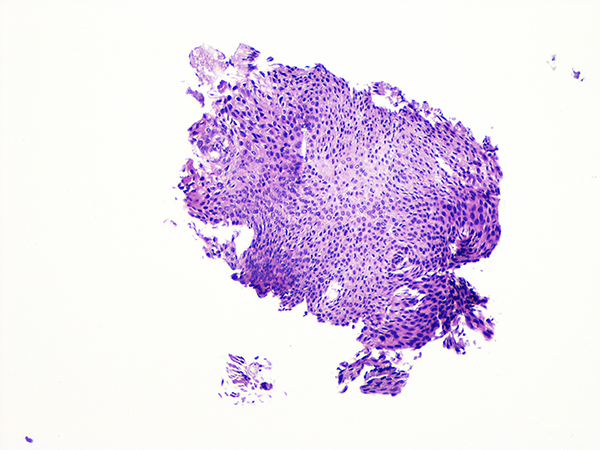

Case 3

Soft Bx CIN 2-3 10x - Low Power